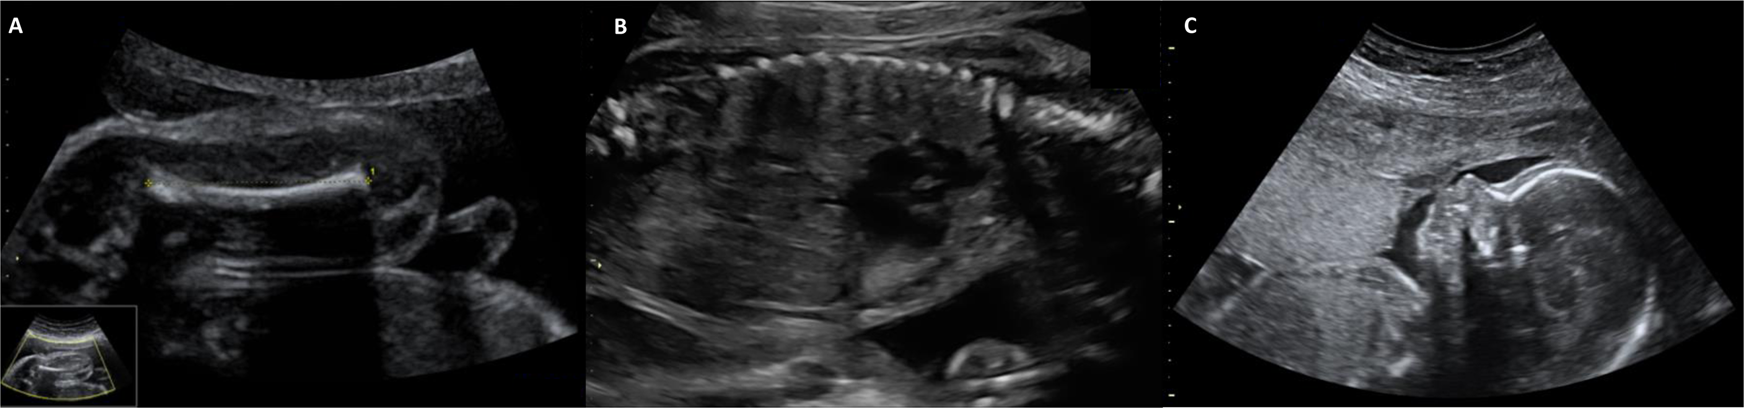

Fig. 2: Ultrasound of the fetus with de novo MN1 variant.

The fetus showed in the 21st gestational week-long bone length under the 3rd percentile (A: femur, 29,3 mm) without any other skeletal abnormalities. During the further course of pregnancy, there have been no other malformation or abnormalities of the skeleton identified (thorax (B) and profile (C) considered as normal; 21st gestational week).